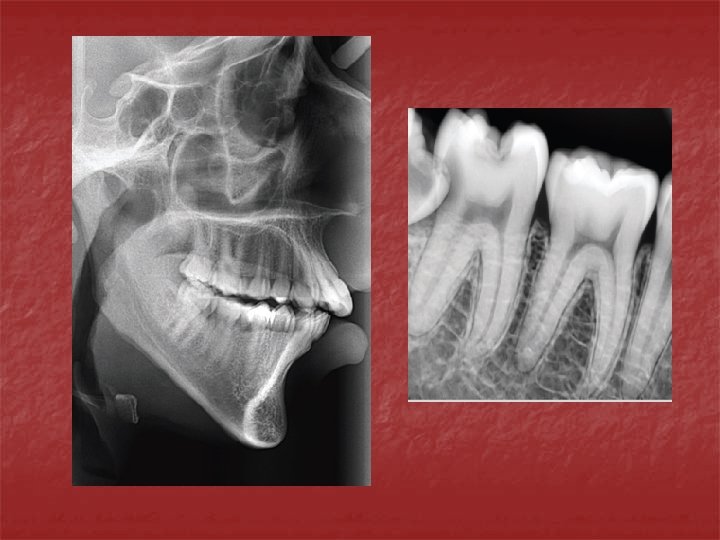

EFECTO DE LAS FUERZAS MASTICATORIAS SOBRE LA INCLINACION DE LAS CÚSPIDES

EFECTO DE LAS FUERZAS MASTICATORIAS SOBRE LA INCLINACION DE LAS CÚSPIDES α R N Resistencia H Componente Horizontal FUERZA MASTICATORIA

n Cuando la inclinación de la cúspide es mayor, la componente de resistencia R se aleja del eje longitudinal del diente y aumenta el componente Horizontal de la fuerza, lo que provoca mayor riesgo de fractura de la cúspide donde está el plano inclinado en el cual incide la fuerza. MAYOR INCLINACION CUSPIDEA MAYOR FUERZA HORIZONTAL

EFECTO DE LAS FUERZAS MASTICATORIAS SOBRE LA INCLINACION DE LAS CÚSPIDES R N Resistencia H Fuerza Masticatoria Componente Horizontal